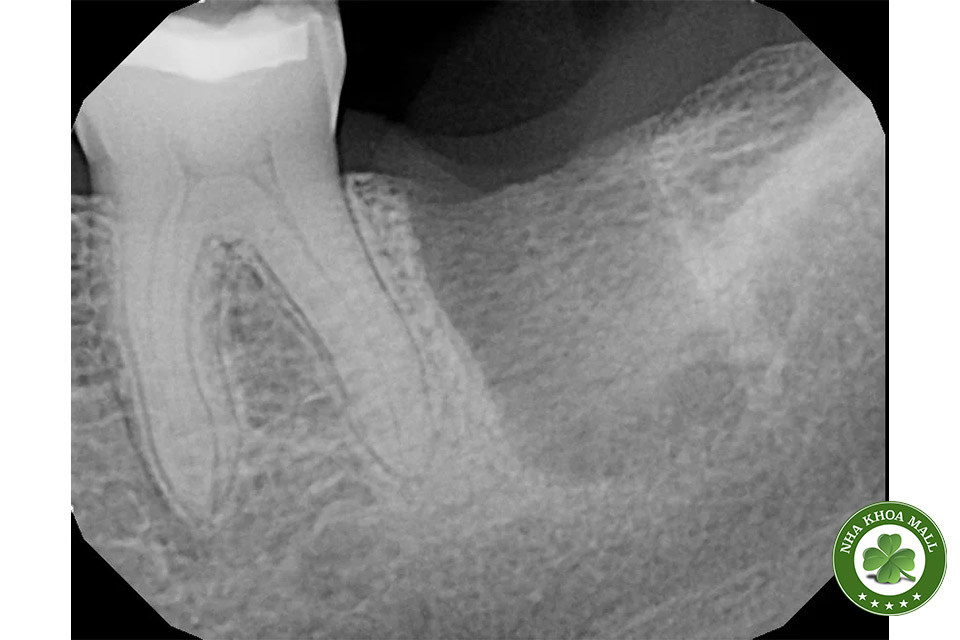

Khi chụp X-quang, bác sĩ có thể nhận thấy một hình dạng giống như ổ chân răng ở vùng đã nhổ, thường là nhiều năm sau khi bệnh nhân có than phiền (Hình 1 và 2). Đây được gọi là ổ chân răng sót lại (residual root socket). Đường viền của ổ chân răng vẫn mờ mờ nhìn thấy, và khi thăm khám phẫu thuật, vùng này có thể rỗng hoặc được lấp đầy bởi mô sẹo xơ đặc, mô hạt hoặc xương non chưa trưởng thành.

(Hình 1: Ổ chân răng sót lại, cho thấy đường viền chân răng cũ của răng hàm lớn – Nguồn: GS Jerry E. Bouquot, University of Texas, Houston.)